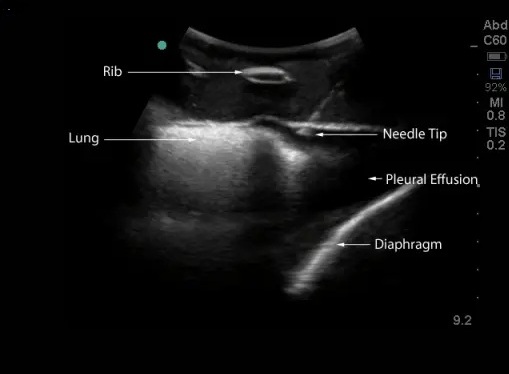

Echographie thoracique

L’échographie thoracique est très utile pour faire le diagnostic des pleurésies et des pneumothorax, l’échographie thoracique en permet aussi la surveillance. C’est un instrument diagnostic très important dans le cas des dyspnées ou essoufflement et douleurs thoraciques.